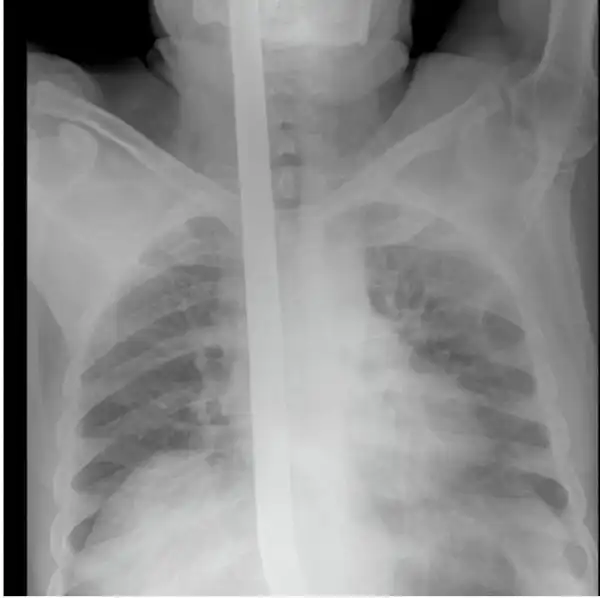

Мужчина упал на лом не повредив жизненно важных органов, говорят после операции выписан в удовлетворительном состоянии домой.

Счастливчик 80 уровня, на снимках и правда видно ни мозг, ни глотку не повредил, везунчик.

Какие ещё оба конца, 3 раза пролистала, то что вы имеете в виду так и не поняла. На всех фотографиях включая рентген пикой внутрь раздвоенной частью наружу.